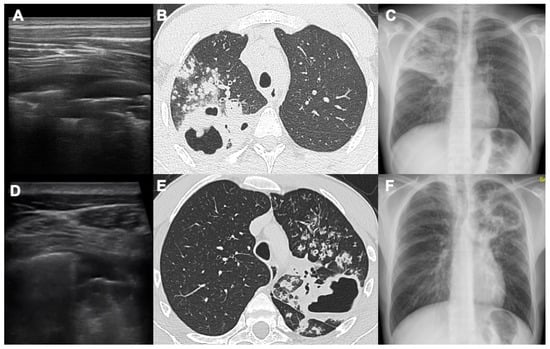

- Giannelli, F.; Cozzi, D.; Cavigli, E.; Campolmi, I.; Rinaldi, F.; Giachè, S.; Rogasi, P.G.; Miele, V.; Bartolucci, M. Lung ultrasound (LUS) in pulmonary tuberculosis: Correlation with chest CT and X-ray findings. J. Ultrasound 2022, 25, 625–634. [Google Scholar] [CrossRef]